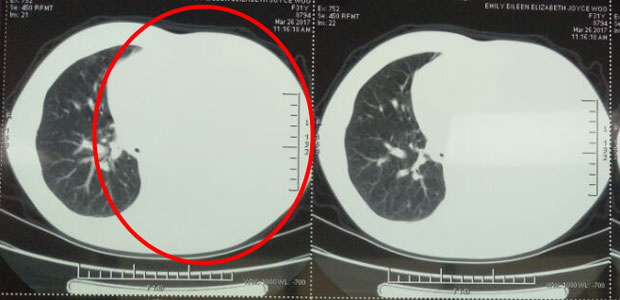

Emily thought she could live a healthy life with her family after operation. However, she didn’t expect misdiagnose to happen on her. In September 2016, she began to cough, and as time went by, her cough got worse so she went to see a doctor. CT scan indicated that there were another 3 tumors in her lungs, the largest tumor in the bottom of her left lung got to 7*5cm and the two other are smaller, about 3cm. Emily was annoyed then because doctor told her before her operation in 2014 that the small mass in her lung was born with her and had nothing to do with cancer.

In March, fluid in her lungs